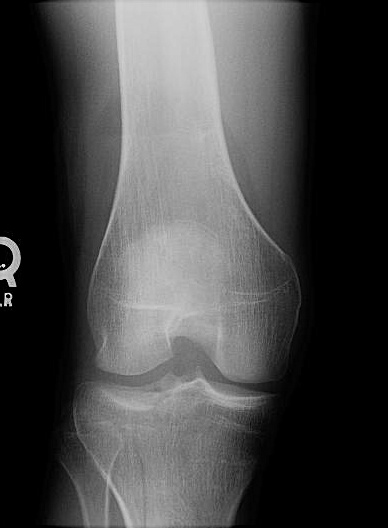

KNEE - AP RADIOGRAPH

This standing AP radiograph of the right knee demonstrates a fat-blood interface in the suprapatellar recess of the knee joint. There is a minimally displaced fracture of the lateral tibial plateau and proximal tibia.